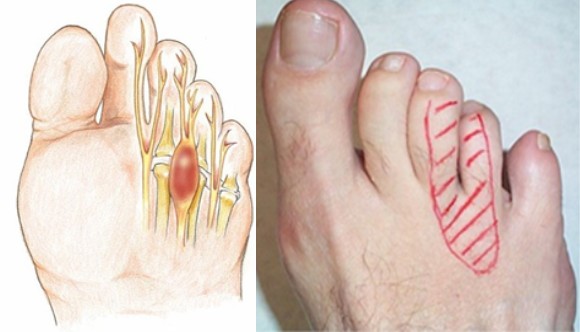

• механическое воздействие на стопу, в результате которого кости начинают сдавливать нерв между средним и безымянным пальцем;

Это лишь основные факторы, которые приводят к развитию Мортона невромы. Существует множество факторов, которые приводят к передавливанию нерва на стопе, и все они связаны с тем, что пальцы стопы находятся в сжатом состоянии, а нерв, расположенный между ними, сдавливается. Патология чаще встречается у женщин, ввиду того, что они носят тесную, подчас очень неудобную, обувь на высоких каблуках.

Один из методов хирургической операции невромы Мортона – ее полное удаление. Неврома представляет собой уплотненную часть нерва, поэтому чтобы удалить уплотнение, врач иссекает часть нерва, которая была повреждена воспалением. Минус данной операции заключается в том, что удаление участка нерва приводит к тому, что на среднем и указательном пальце появляется постоянное чувство онемения. Человек его не почувствует, пока не дотронется до этих пальцев, но часто этого никто не делает, поэтому данное осложнение не приносит никакого дискомфорта. Функция самой стопы остается без каких-либо изменений, движение пальцев не ограничивается.

Для проведения операции по удалению невромы стопы используется местная анестезия. Врач иссекает кожу и мягкие ткани на месте расположения поврежденного участка нерва. Разрез делается небольшой – до 2 см. После того, как частица нерва была иммобилизована и иссечена, врач зашивает рану и накладывает стерильную повязку.